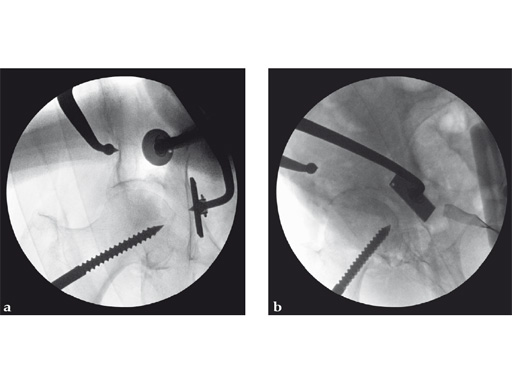

Fig 2ab Intraoperative AP hip and iliac oblique image intensifier images of a portion of the reduction sequence utilizing distal/lateral traction through a Schanz screw, ball spike (picador) with disc and asymmetrical reduction clamp with disc. The remaining area of incompletely reduced articular surface was a free, thin osteochondral fragment retrieved through the anterior column fracture. It was reoriented and trapped between the lateral articular surface, displaced anterior column, and femoral head. Despite multiple attempts this position could not be further improved. Cancellous autologous bone graft was used to buttress this area through a small internal iliac fossa cortical window.